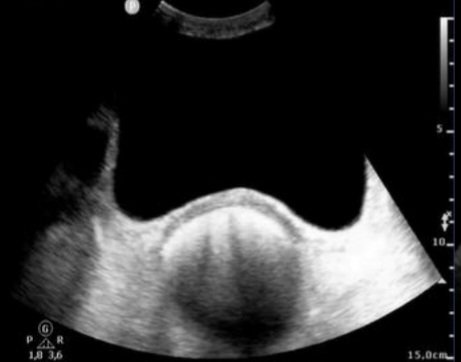

@DrStarWolf @ChampoDr @duran_georg @132_dc @DrGroquik Sans problème, c'est archi-débile. Se et VPN proche de 100%, permet de surseoir au TR. En transversal et longitudinal : image hyperéchogene colique rétro-vésicale avec cône d'ombre post, lignes B possibles si un peu d'air.

TheFrenchPOCUS tweet mediaTheFrenchPOCUS tweet media